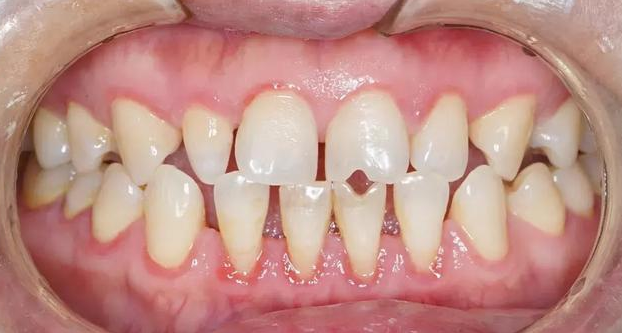

廊坊圣洁口腔医院的医生说,过小牙是指小于正常牙的牙齿,形态多为锥形,且明显小于正常的侧切牙,有碍美观,有时也会影响发音和切咬功能。

过小牙有个别牙过小和普遍性牙过小,其病因多与遗传有关。普遍性牙过小多见于脑垂体功能低下的侏儒症,临床比较罕见。有的牙过小与缺牙症同时存在,或伴随一些结构异常与萌出异常,有的是综合征的一个表现。绝大多数外胚叶发育不全的遗传病都会累及牙齿,例如无汗型或少汗型外胚叶发育不全,除无汗、缺汗等外还出现部分或全部无牙、牙齿过小并呈锥形等异常现象。 》》》推荐阅读:廊坊市民牙齿美容冠是什么

过小牙会严重影响一个人的容貌、气质,不仅对唇型、脸型会产生影响,而且让人会由于牙齿排列不整洁而表现得不够自信,不仅不敢笑,就连说话也得遮遮掩掩,危害身心健康。

2.易造成口腔疾病

过小牙的牙面凹凸不平,牙与牙之间的不良接触容易造成不易清洁区域,很轻易滞留牙菌斑、食品残渣。从而导致牙龈炎、牙结石、牙面色素沉着、口臭、龋坏等口腔疾病。 》》》推荐阅读:美齿不磨牙——廊坊市民全瓷贴面